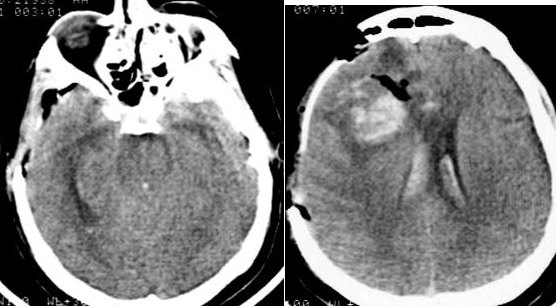

Через два часа после операции выявлялись: угнетение сознания до уровня комы II, орально-стволовый синдром, левосторонний гемипарез. Было выполнено контрольное КТ-исследование, при котором выявлялся отек головного мозга с компрессией базальных цистерн, сохранялась гематома в лобно-височной области справа и желудочковой системе (Рис. №3). По данным ТКДГ, определялось нарастание вазоспазма в бассейнах СМА и ПМА справа (Табл. №2).

На третьи сутки после операции была отмечена положительная динамика: кома I, частичный регресс левостороннего гемипареза. При проведении КТ-исследования головного мозга выявлены признаки санации ликвора в виде снижения плотности крови в желудочковой системе, уменьшение размеров гематомы правой лобной области. Базальные цистерны прослеживались более четко, зон пониженной плотности вещества мозга выявлено не было (Рис. №4).